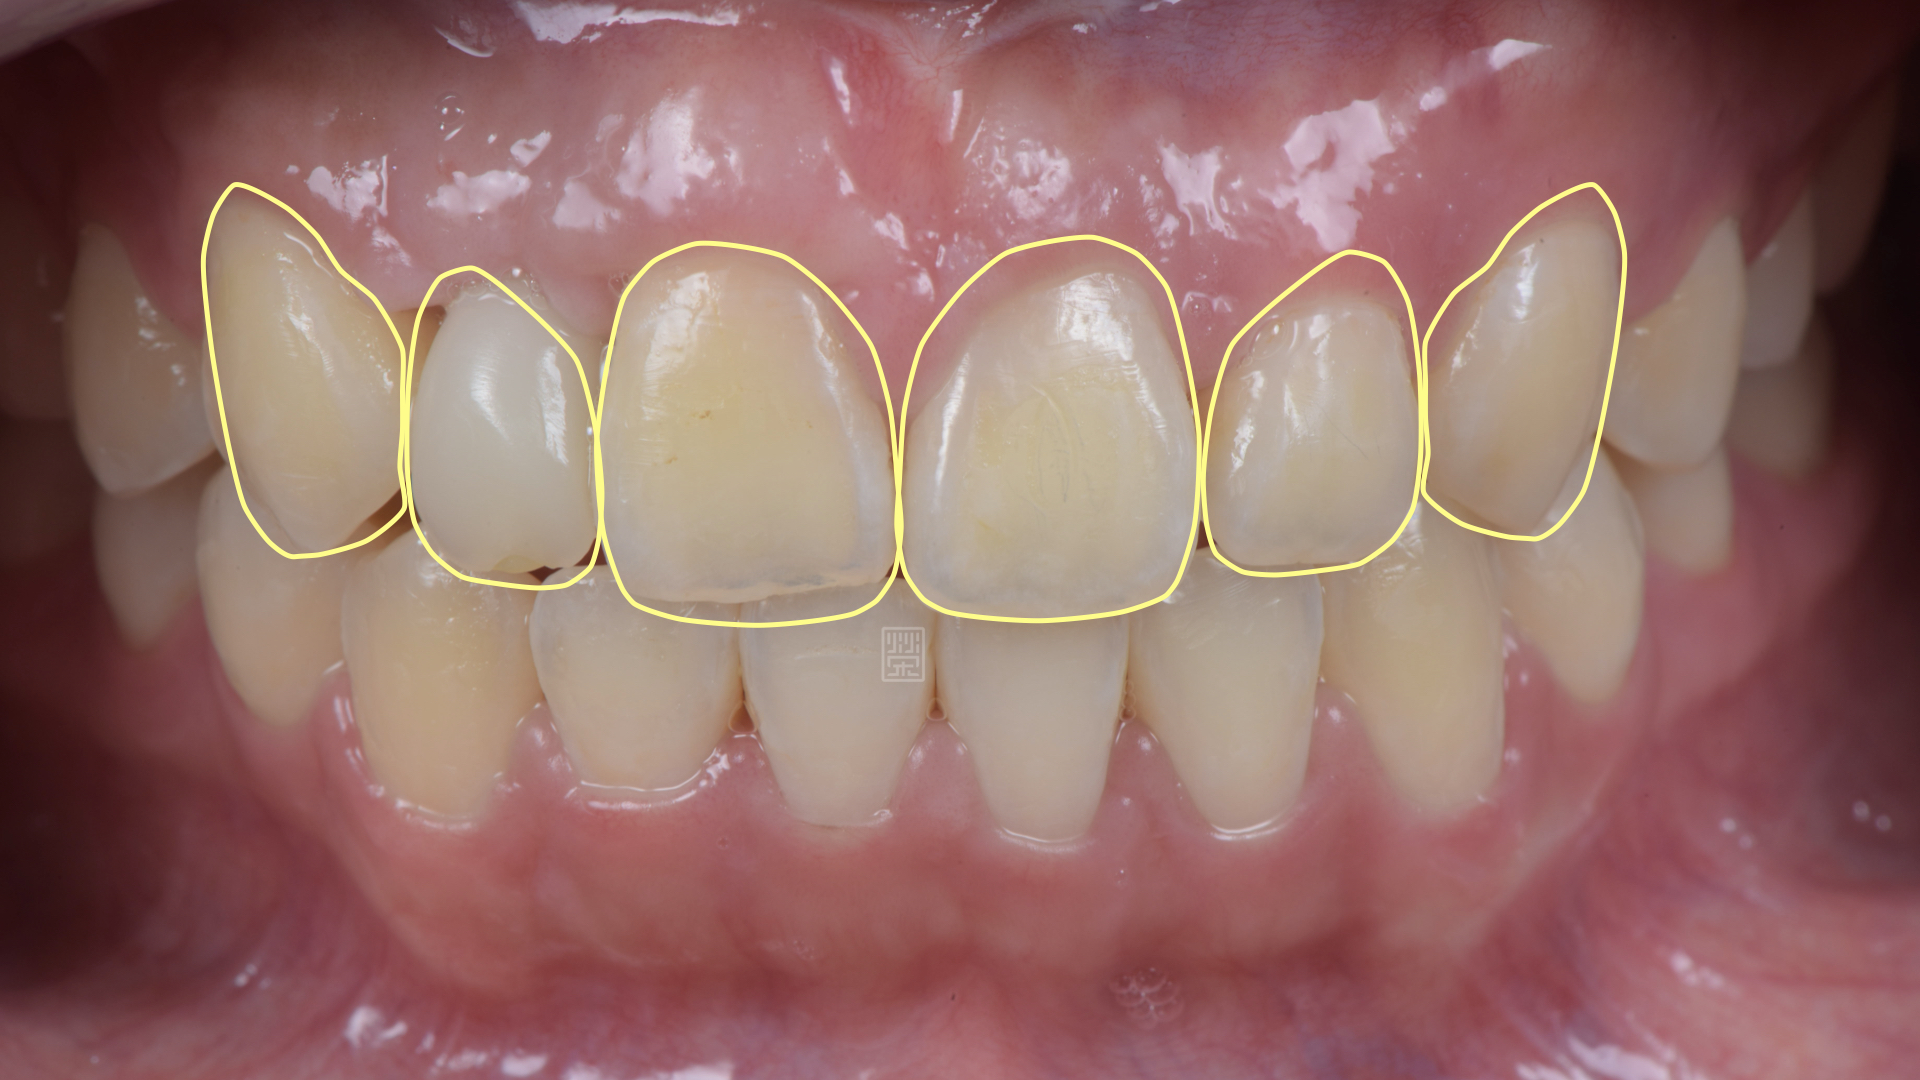

全瓷冠位置、牙齦線位置評估